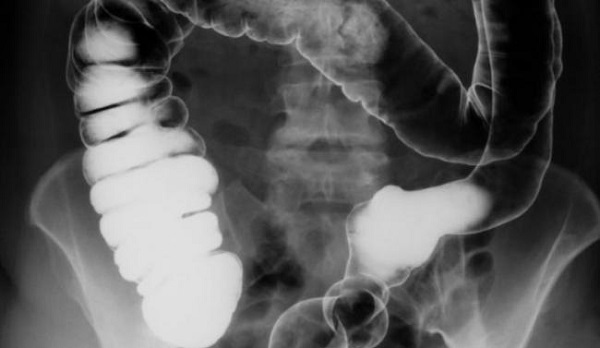

Chụp X quang đại tràng dùng thuốc cản quang

Chụp X quang đại tràng dùng thuốc cản quang là kỹ thuật làm cản quang khung đại tràng bằng dịch treo Baryt. Để thực hiện phương pháp này, bệnh nhân phải đảm bảo thụt tháo ruột sạch hoàn toàn trước khi cho thuốc đối quang vào. Đây là một trong những phương pháp giúp phát hiện những bất thường ở đại tràng, trong đó có ung thư.

Người khám được chụp với nhiều tư thế khác nhau, hình ảnh của các đoạn đại tràng như sigma, trực tràng, góc lách trái, góc gan, manh tràng, đại tràng lên… được ghi lại để bác sĩ đánh giá tình trạng tổn thương của mỗi người.

Phình đại tràng bẩm sinh (Hirschsprung) là bệnh lý gây táo bón mạn tính ở trẻ em do vô hạch đại tràng. Hình ảnh qua chụp X quang đại tràng dùng thuốc cản quang bằng baryt cho hình ảnh đại tràng sigma giãn to, trực tràng teo nhỏ, đại tràng dài ra, thuốc ngấm không đều ở đoạn vô hạch.

Là bệnh ung thư đường tiêu hóa phổ biến hàng đầu ở nữ giới và thứ ba ở nam giới. X quang đại tràng thường được xem xét khi nội soi đại trực tràng thất bại. Với phương pháp chụp đối quang kép có thể phát hiện những tổn thương nhỏ. Hình ảnh phim chụp có thể qua sát thể sùi vào lòng (hình khuyết bờ không đều), thể thâm nhiễm hay thể loét… Để đánh giá chính xác tình trạng bệnh, các bác sĩ thường phải kết hợp với nhiều phương pháp chẩn đoán chuyên sâu khác.